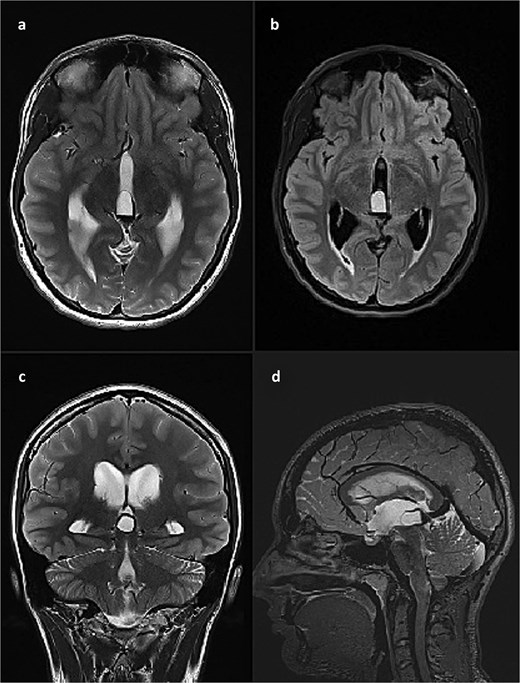

She was admitted to the hospital and an external ventricular drainage was placed in the right lateral ventricle for the treatment of hydrocephalus. The procedure was uneventful and, at that time, ameliorated her symptoms. Five days later, the patient was subjected to a surgical excision of the pineal gland cyst. She was operated on in a sitting position with her neck slightly flexed and head fixed rigidly with the Mayfield head clamp, using a SCIT approach in its standard fashion. Her postoperative recovery was uneventful, with the postoperative head CT scan and brain MRI showing no signs of hemorrhage or tumor residues (Fig. 3).

Postoperative brain MRI scan showing no residual tumor. (a) T2 weighted image, axial slice; (b) FLAIR image, axial slice; (c) T2 weighted image, coronal slice; (d) T2 weighted image (SPACE), sagittal slice).